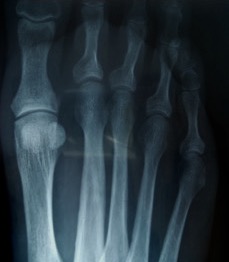

- anatomic anomaly e.g. relatively long 2nd MT compared to the 1st MT (Figure 1)

Figure 1: DP radiographic view of a long 2nd metatarsal